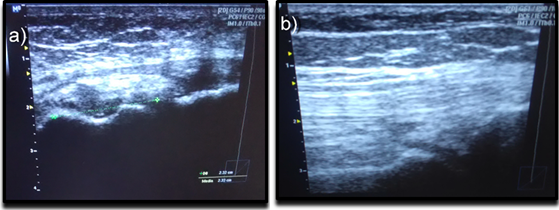

Figure 5b shows that the therapy applied to the second experimental group reduces the inflammation of the ligaments and pain since it inhibits pain and inflammation in the patients/sportsmen and with an effectiveness of more than 70 % in comparison with the conventional therapy Figure 5a; facilitating their rapid reincorporation into social life. The anti-inflammatory effects of (magnetostatic field + cryotherapy) have been explained by inhibiting pro-inflammatory enzymes (interleukins IL-2 and IL-6) and stimulating anti-inflammatory enzymes (interleukin IL-10); since it reduced functional impairment and synovial inflammation of the knee by decreasing the amount of leukocytes and the concentration of cytosine in the synovial fluid. The use of the magnetic knee brace for the treatment of SRP was practical, simple, light and portable.17

Figure 5 Ultrasound imaging for SRP therapy. a) Conventional treatment (cryotherapy + ibuprofen + dipyrone) and b) Magnetic treatment (magnetic knee brace + cryotherapy).26